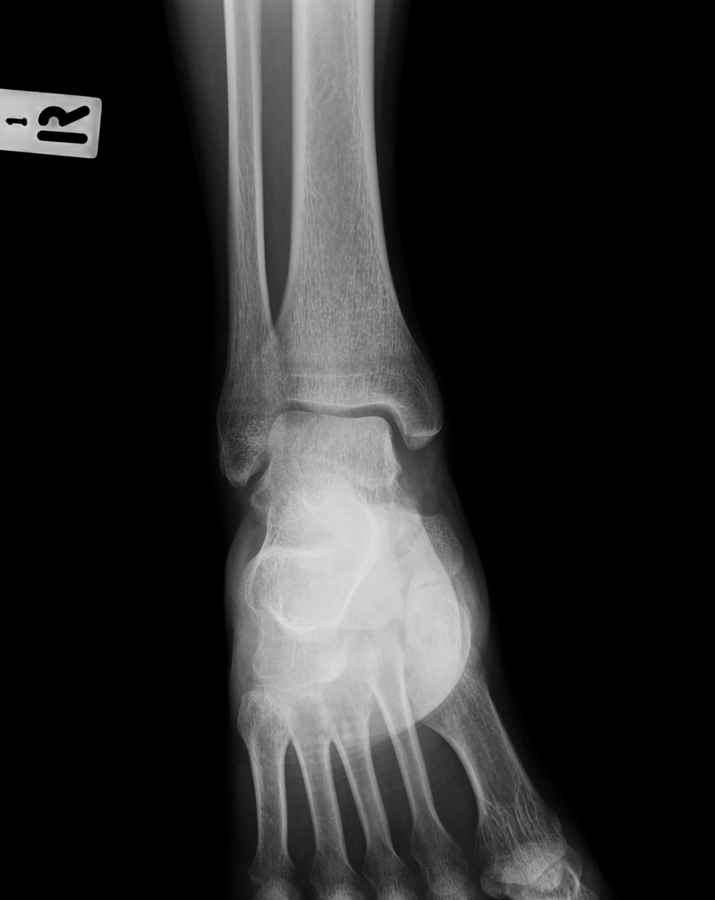

Дорогие коллеги,Мужчина 36 лет, пострадал около 8 месяцев назад в ДТП (водитель мотоцикла).

Подтаранный вывих лечили гипсовой лонгетой. Недиагностированным остался перелом ладьевидной кости, который беспокоит в настоящее время. Аваскулярный некроз кости, похоже. Добавил наиболее значимые снимки, на мой взгляд.

По данным снимкам однозначно сказать о некрозе ладьевидной кости нельзя. Типичные изменения при аваскулярном некрозе ладьевидной кости, как правило, начинаются в центральной её части с дальнейшим развитием коллапса. В данном случае в значительной степени пострадал таранно-ладьевидный сустав, вероятнее всего, именно это является причиной болевого синдрома. При отсутствии эффекта от физиотерапии и ношения ортопедической обуви в течение ближайших 6 месяцев придётся ставить вопрос о таранно-ладьевидном артродезе.